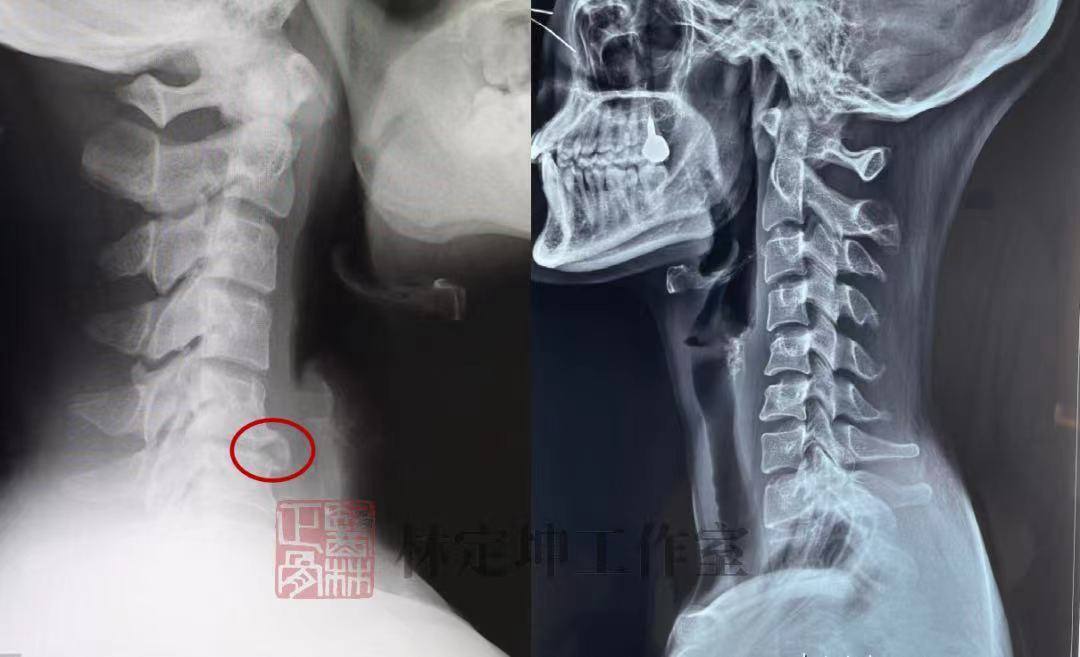

骨质增生(左图)与颈椎生理曲度变直(右图)

(图/林定坤工作室)